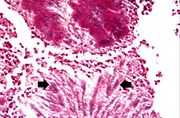

| 04:03, 21 August 2013 | IPLab10Candidiasis4.jpg (file) | 53 KB | This is a low-power photomicrograph of one of the Candida colonies from this lymph node. The chains of yeast which are termed "pseudohyphae" are apparent at this magnification. | 1 | |